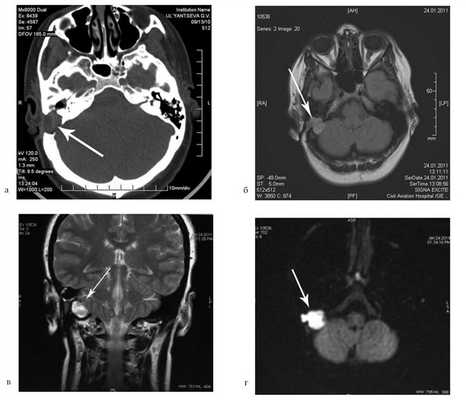

На КТ височных костей справа послеоперационная полость, заполненная мягкотканным образованием, определяется большой костный дефект в направлении сигмовидного синуса и мозжечка (рис. 2, а). Рисунок 2. КТ и МРТ височных костей больной У. с хроническим правосторонним средним отитом. Состояние после радикальной операции (1993 г.), санирующей операции с мастоидопластикой и тимпанопластикой (2003 г.). Холестеатома. Парез лицевого нерва. а — КТ; б — МРТ основания черепа в режиме Т1; в — в режиме Т2; г — в режиме non-EPI DWI.

Больной была выполнена МРТ (рис. 2, б—г).

В режимах Т2 и non-EPI DWI определяется сигнал высокой интенсивности, в режиме Т1 — низкоинтенсивный сигнал. Это может свидетельствовать о наличии холестеатомы мастоидальной полости и пирамиды височной кости. Диагноз: хронический правосторонний средний отит; состояние после радикальной операции в 1993 г. и санирующей операции с мастоидопластикой и тимпанопластикой в 2003 г.; холестеатома; парез лицевого нерва.

Больной произведена санирующая реоперация, в ходе которой удалена холестеатома больших размеров, заполняющая отшнурованную послеоперационную полость. Эта полость распространялась до верхушки сосцевидного отростка, граничила с твердой мозговой оболочкой и достигала верхушки пирамиды височной кости. Полость облитерирована. В послеоперационном периоде получен хороший функциональный результат. Ухо толерантно к воде, не было обострений, гноетечения, головокружений. Сохранилась кондуктивная тугоухость I степени. МРТ через 9 мес подтвердила отсутствие холестеатомы.

На КТ правой височной кости определяется затемнение в области аттика и антрума, цепь слуховых косточек сохранена (рис. 3, а). Рисунок 3. КТ и МРТ височных костей больного А. с адгезивным средним отитом справа, фиброзной облитерацией аттика. а — КТ; б — МРТ основания черепа в режиме Т1; в — в режиме Т2; г — в режиме non-EPI DWI.

Пациенту выполнена МРТ основания черепа по описанной методике (рис. 3, б—г).

В режиме Т1 и Т2 справа определяется очаг с высокой интенсивностью сигнала, тогда как в режиме non-EPI DWI патологических образований не выявлено. Диагноз: адгезивный средний отит справа, фиброзная облитерация аттика.

В связи с отсутствием данных о холестеатоме операция не производилась, выявленные изменения расценены как фиброзные изменения, оторея была обусловлена периодическим возникновением наружного отита. Больной получал консервативное лечение.